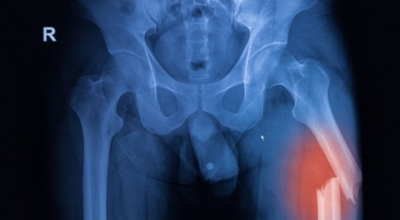

글루코사민에 비해 원료가 100배가량 비싼 고가의 원료인것으로 알려져 있어요. 관절염 원인으로는 관절 연골이 닳아 없어지기 때문인데 퇴행성 질환이라고 부르는 이유가 연골이 더 이상 생성되기 어렵기 때문이지요. 특히나 콘드로이친이라 하는 성분이 나이가 들면서 길이가 짧아지고, 크기가 줄어들기 때문에 연골 구조가 바뀌어 가면서 무릎뼈의 간격이 좁아져 통증을 유발하는 원인인데 이때 콘드로이친 효능을 바라볼 수 있어요.

6. 콘드로이친 효능 - 골관절염

콘드로이친은 보통은 골관절염 증상 관리를 위한 치료제로 사용되고 있어요. 미국에서 시행된 골관절염 환자 604명을 대상으로 한 연구에서 콘드로이틴의 골관절염 통증 관리의 효과를 관찰했는데 그 결과, 콘드로이틴이 무릎 골관절염 통증이 있는 이들의 약 10%가 통증완화와 개선효과를 체험했어요.

그 이유는, 노화가 진행되는 중장년층에게서 콘드로이친 수치가 저하되는걸 볼 수 있어요. 이는 곧 연골의 뼈와 뼈 사이 완충효과 또는 보호기능 약화로 이어지는데 이를 보충하면 관절염을 해결하는데 도움을 주어요. 그리고 콘드로이친은 관절세포를 재생시키는데 도움을 주며 외부 충격을 흡수, 개선하는데에도 뛰어난 효과가 있어요.